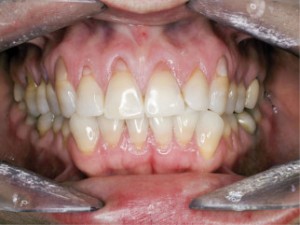

| Pacjentka w wieku 40 lat przed leczeniem. Mnogie (wysokie i szerokie) recesje dziąsła, ryc. 1 | Pacjentka w wieku 40 lat przed leczeniem. Mnogie (wysokie i szerokie) recesje dziąsła, ryc. 2 | |